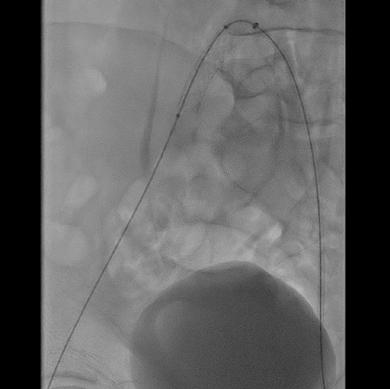

TAME was performed via an ipsilateral antegrade femoral approach and patients were evaluated for all target branches of the posterior tibial artery and peroneal artery.